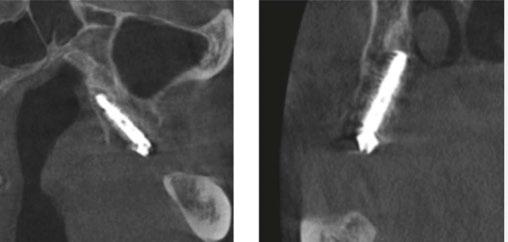

Due to the atrophic nature of the maxilla, treatment following the PATZi protocol was planned.6,17,20 CBCT evaluation revealed pterygomaxillary bone appropriate for pterygoid implants allowing for posterior arch support and cantilever elimination. The zygomas were of adequate height and width to accommodate multiple zygomatic implant fixtures bilaterally. PLACATE guidelines were used to evaluate the patient for potential treatment with transnasal implants. With Simmen 3 nasolacrimal canal classification, ≥ 3 mm of prelacrimal bone, ≥2 mm subnasal bone, and ≤ 25 mm to the Z-point, the patient satisfied all PLACATE parameters. Accordingly, a treatment plan of bilateral pterygoid, single zygomatic, and transnasal implants was agreed upon.

Following the induction of general anesthesia, extraoral and intraoral local anesthesia was applied. To avoid exposing the large subantral bony defects, mini-flaps were elevated at the pterygoid landing areas to expose the hamular notch. The pterygoid fossa was identified via probing, and pterygoid implant placement ensued. Following the PATZi protocol, bilateral pterygoid implants were placed first and both achieved insertion torque between 45+ Ncm.

Following PATZi, anterior support was sought next. As such, the nasal mucosa was elevated to expose the floor of the nasal cavity and the bone of the inferior conchae. A pair of 25 mm transnasal implants were placed, and each achieved high insertion torque of 45+ Ncm (Figures 9-11). Continuing with the PATZi protocol and treatment plan, 42.5 mm long zygomatic implants were placed in both zygomas. The zygomatic implants were placed using an extrasinus approach and both achieved insertion torque of 45+Ncm. Buccal fat pedicles were advanced bilaterally to cover extrasinus portions of the zygomatic implants, and flap closure was achieved with 4-0 chromic gut suture. The patient was immediately temporized with a screw-retained transitional bridge (Figure 12), and a final zirconia restoration was delivered after 8 months of healing (Figure 13).

Figure 10 (left): CBCT slice (coronal view) of transnasal dental implants engaging the Z-point. Figure 11 (middle): CBCT slice (sagittal view) of transnasal dental implant engaging prelacrimal bone ventral to the nasolacrimal duct. Figure 12 (right): 3-dimensional CBCT rendering of patient treated with transnasal, zygomatic, and pterygoid dental implants via the PATZi protocol